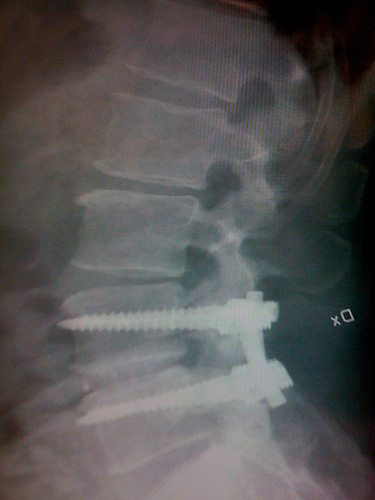

If were getting our excuses in early, heres mine

Attached Thumbnails

Click image for larger version Name:	5514762074_c4041cbc61.jpg Views:	112 Size:	115.3 KB ID:	12340

Ouch!

Originally Posted by Bionicle